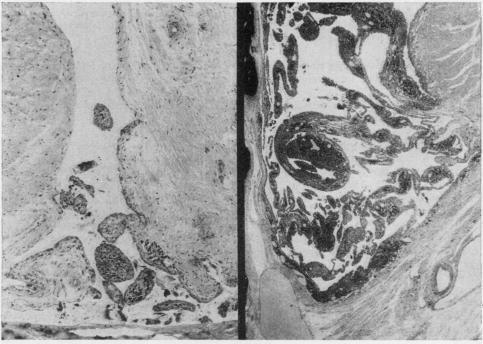

Seventeen rabbits were immunized with complete Freund's adjuvant and bovine serum albumin by the method of Dumonde and Glynn (1962), as modified by Cooke and Jasin (1972). Fifteen weeks after allergic arthritis developed in the knee joint, 8 animals were given an injection of 20 muCi yttrium 90 (90Y) into the left joint cavity; 7 were injected with 400 muCi. The animals were sacrificed at 2, 4, 8, 12, and 16 weeks and at 6 and 12 months after the injection. The right knee joint served as control for assessment of untreated allergic arthritis. Morphological control of the severity of the arthritis was provided by sacrificing 2 uninjected animals 13 weeks after immunization.

按照杜蒙德和格林(1962年)的方法,并经库克和贾辛(1972年)改良,用完全弗氏佐剂和牛血清白蛋白对17只兔子进行免疫。膝关节出现过敏性关节炎15周后,给8只动物的左关节腔内注射20微居里钇90(90Y);7只动物注射400微居里。在注射后2周、4周、8周、12周、16周以及6个月和12个月处死这些动物。右膝关节作为评估未经治疗的过敏性关节炎的对照。在免疫13周后处死2只未注射的动物,以提供关节炎严重程度的形态学对照。